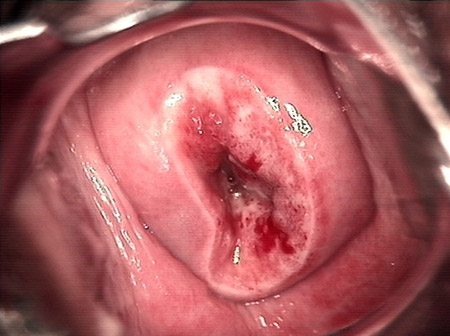

婦科leep錐切手術(shù) CIN2-3

• CIN 2-3CIN 2-3